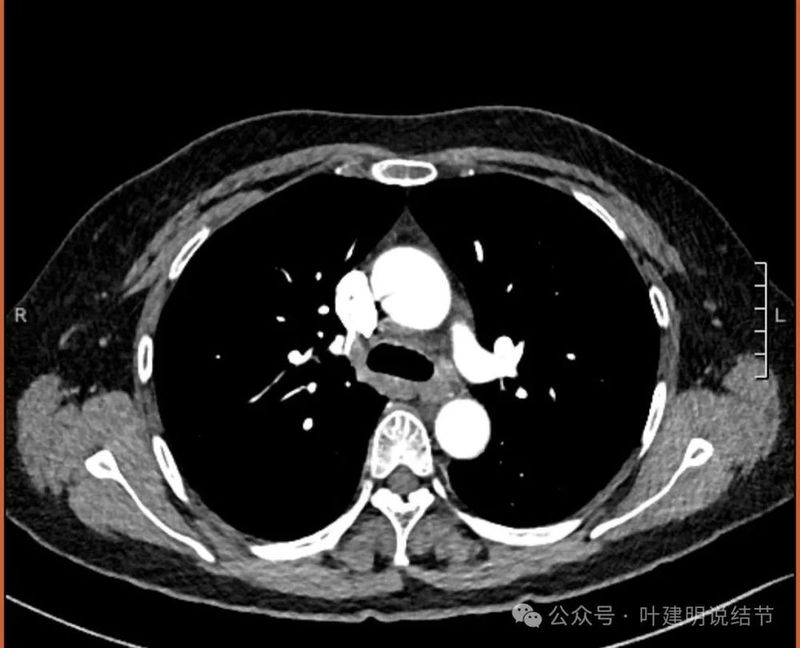

纵隔与肺门没有见到显著增大融合要考虑转移的淋巴结。